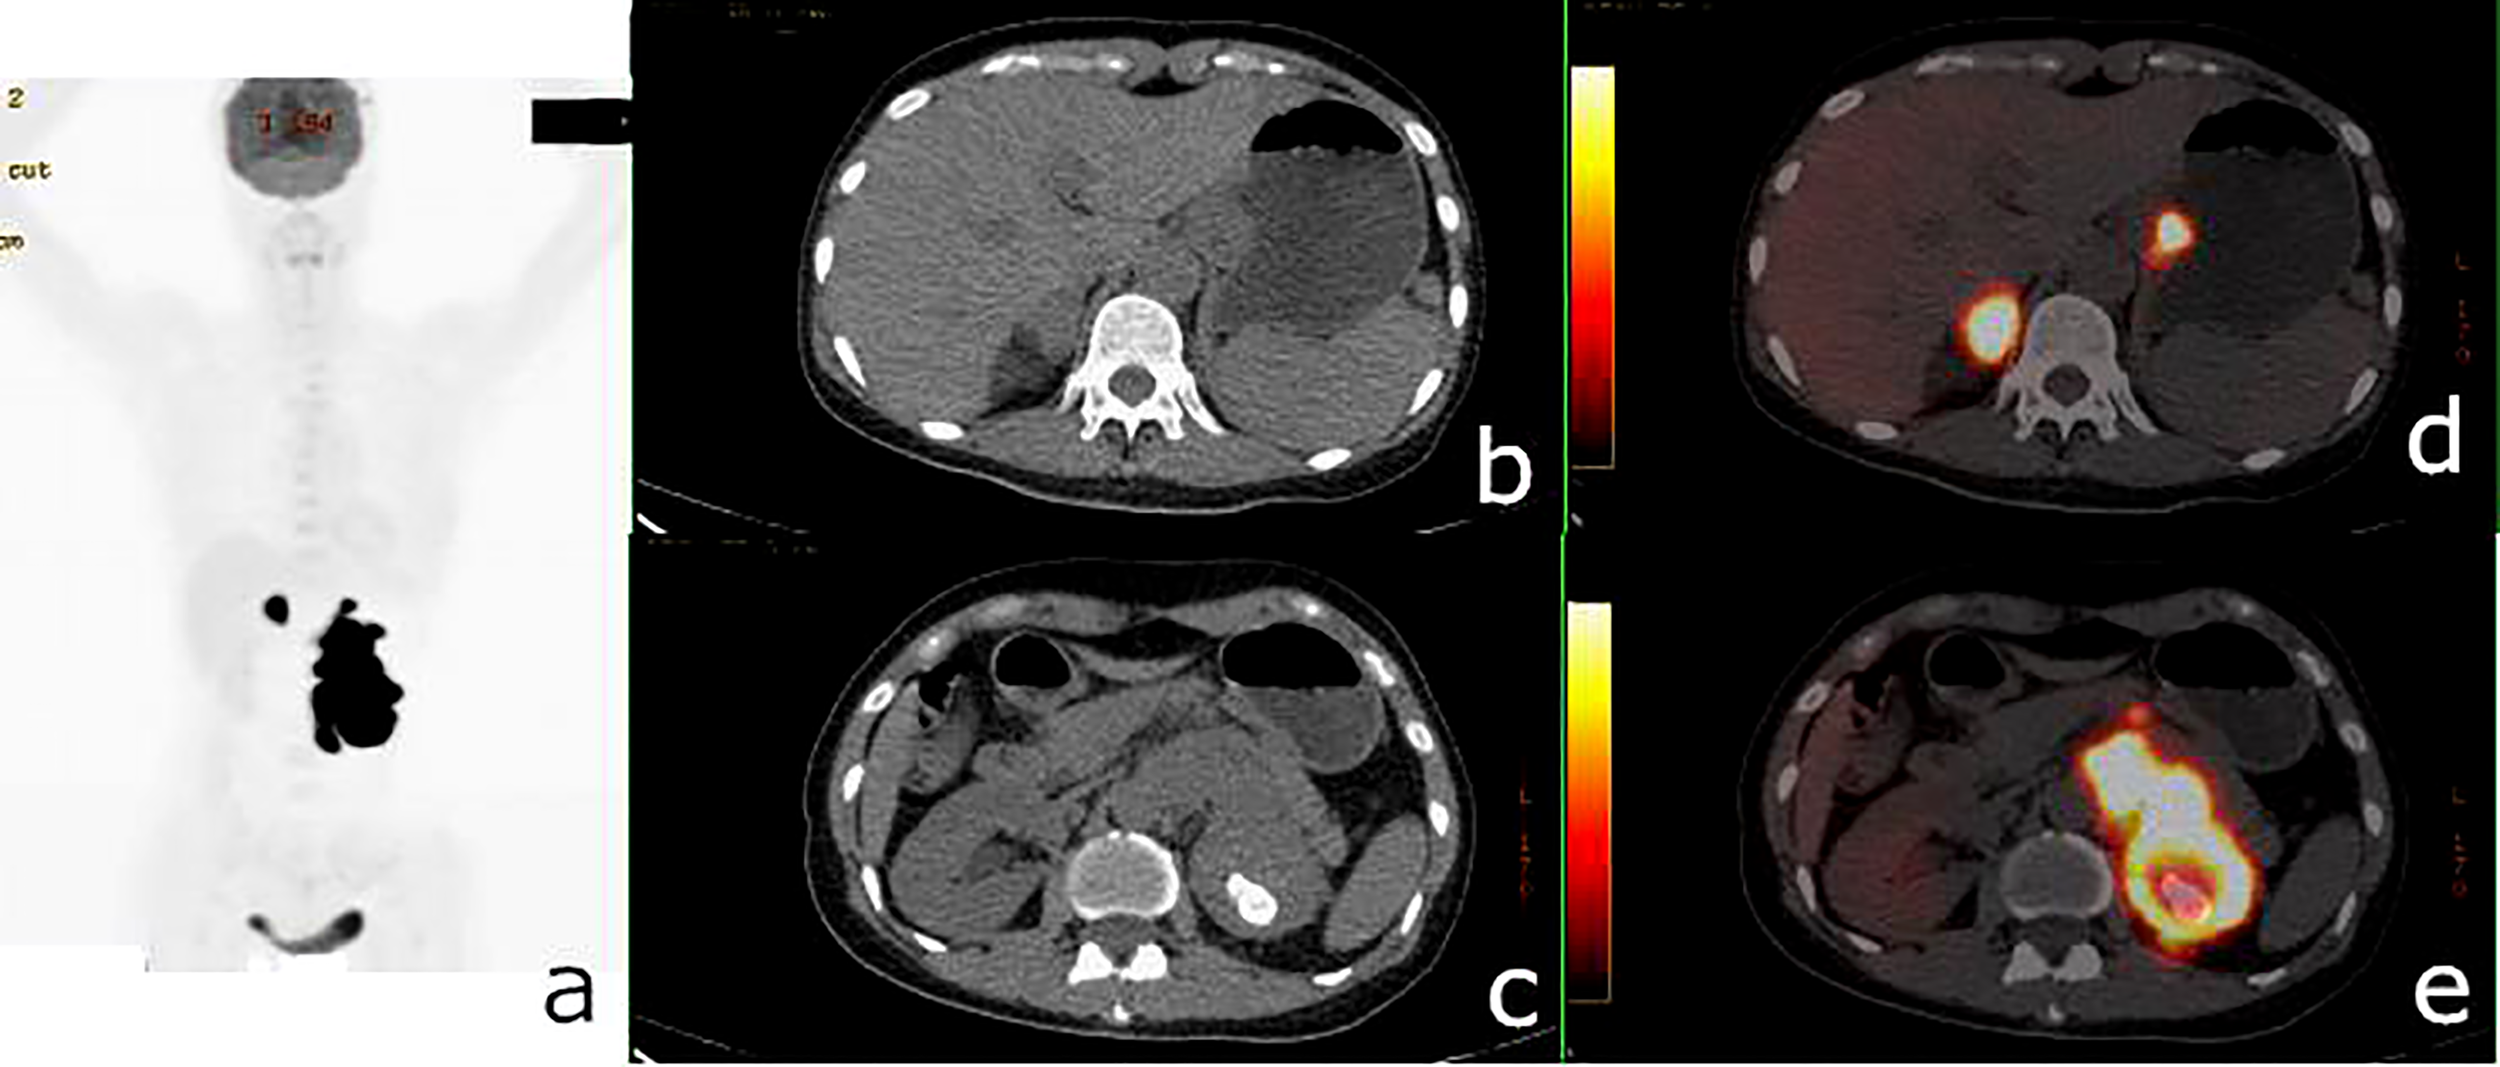

FIGURE 3

Figure 3 18F-fluorodeoxyglucose positron emission tomography/computed tomography (18F-FDG PET/CT) of a 62-year-old man with lung adenocarcinoma and hepatocellular carcinoma. PET/CT revealed a lobulated mass with central FDG uptake (maximum standardized uptake value, SUVmax = 8.9) and a 48 × 49-mm hypodense mass with SUVmax = 2.0 in the right hepatic lobe (white arrows). (A): PET maximum maximum intensity projection (MIP). (B, C): Axial CT. (D, E) Fusion images.